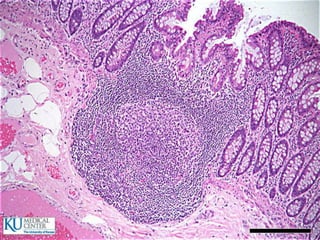

Intestino Grueso

 180cm de largo

 El material alimenticio entra en estado semilíquido y

sale semisólido

 Función:

 Absorción de líquido

 Secreción de moco